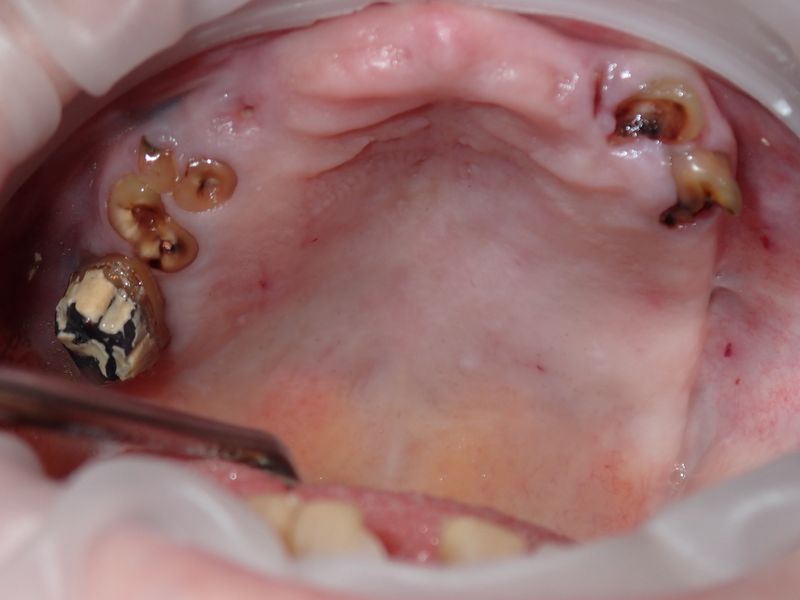

fredlibc | all galleries >> Galleries >> MWang - upper arch graft > P1200002.JPG

P1200002.JPG